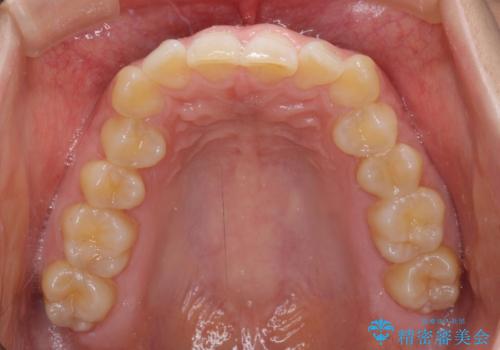

- 上顎前歯の前方に傾斜した咬み合わせを気にして来院された患者様です。

奥歯の咬み合わせを見ると、上顎が下顎に対して相対的に前方にありました。

深い咬み合わせを改善するためには、上顎臼歯を後方に移動させつつ、下顎の小臼歯を直立させる必要があります。

インビザライン単体で対応ることも検討できますが、達成する可能性が低いため、カリエールディスタライザーという補助装置を併用して、より確実性を上げることとしました。

奥歯の咬み合わせと深い咬み合わせを改善した後、インビザラインで歯列を整えることとしました。